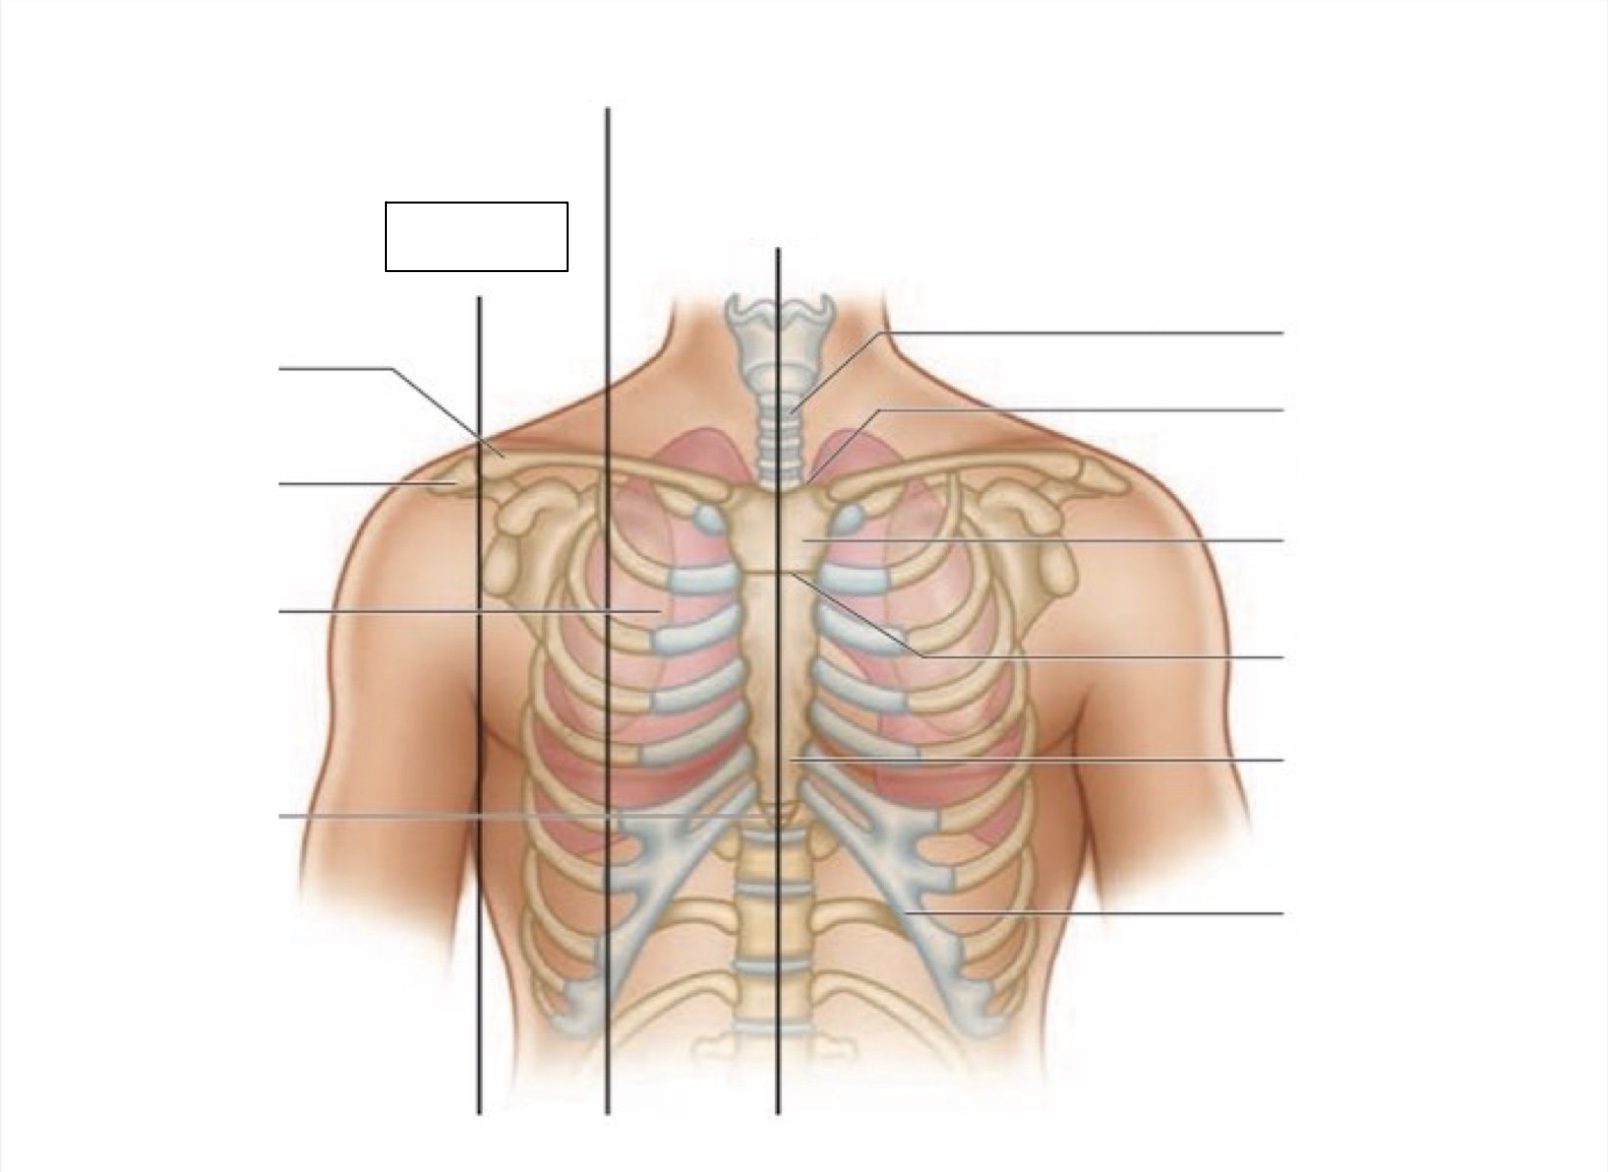

midsternal line

trachea

suprasternal notch

manubrium

angle of Louis

sternum

costal margin

xiphoid process

intercostal space

acromion

clavicle

anterior axillary line

midclavicular line

inferior angle of scapula

scapula

midscapular line

midspinal line

spinous process